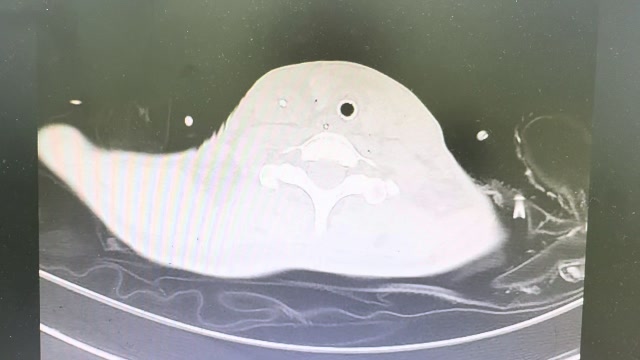

2023年10月26日,来自山东菏泽市成武县的小烨和他家人的命运被彻底改变了。这个原本阳光、可爱的小男孩在一次意外被撞击后,在医院检查出了腹腔内存在肿瘤,并在手术中被切除了包括十二指肠、胰腺、大部分胃和小肠等多个器官。此后便无法再像正常人一样吃饭、喝水,活着要靠长期静脉注射营养液。一份2024年12月由第三方机构出具的司法鉴定意见书显示,当时给小烨做手术的成武县人民医院在该医疗行为中存在过错,与小烨的损害后果之间存在因果关系,建议医疗过错在损害后果中的原因力大小为同等原因。此外,另一份由成武县卫生健康局在2025年9月28日发出的书面答复中显示,成武县人民医院存在24小时内未完成病历;手术知情